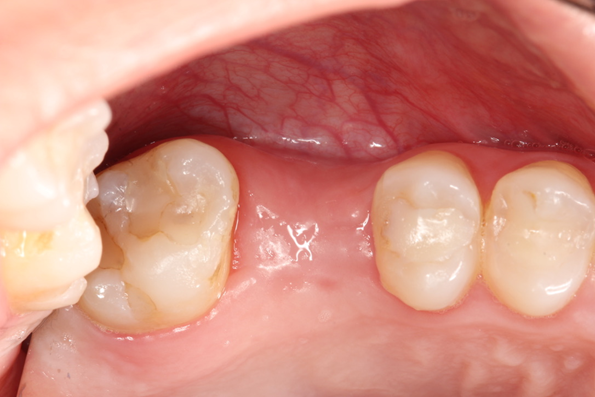

Paciente C.B.F.J., 33 anos, leucoderma, não-fumante e em boas condições de saúde sistêmica, relatou sensibilidade dolorosa durante mastigação no elemento 26, que já possuía tratamento endodôntico, pinos metálicos intrarradiculares e coroa metalocerâmica (Figura 1). Foi solicitada tomografia computadorizada de feixe cônico, na qual a imagem sugeriu fratura radicular na região da furca, descontinuidade óssea da cortical de seio maxilar e opacificação parcial do seio maxilar esquerdo (Figura 2). Foi realizada a exodontia e pôde-se confirmar a comunicação oroantral (Figura 3). Após curetagem do alvéolo, sem preocupação em curetar e remover a lesão cística sinusal, uma barreira reabsorvível foi recortada e posicionada no fundo do alvéolo para obliterar a descontinuidade óssea e impedir que células de tecido mole oriundas da cavidade sinusal invadissem a região alveolar (Figura 4). O alvéolo foi preenchido totalmente por coágulo sanguíneo do paciente (Figura 5) e o alvéolo foi selado por uma barreira não-reabsorvível (Figura 6), impedindo a invasão de fibroblastos do tecido gengival para dentro do alvéolo. Após duas semanas, a barreira estava estável e, então, foi removida, desnudando um tecido de granulação osteoblastogênico (Figura 7).